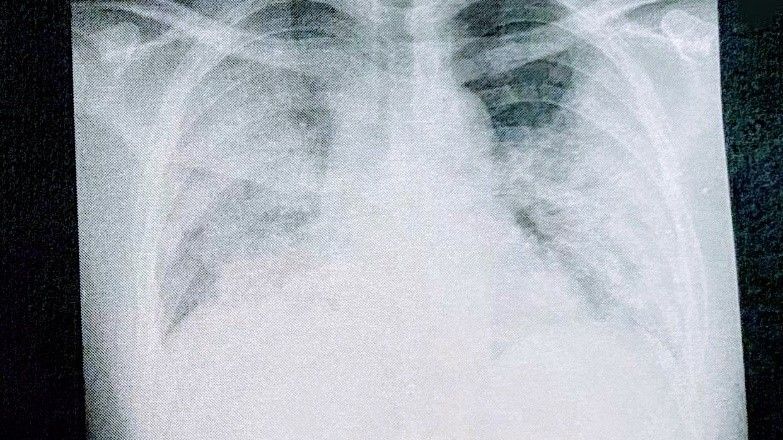

「もう助からない」専門家ですらそのように見えたほど真っ白になった肺。これが37歳のコロナ患者が味わった現実だ(写真:取材者提供)この記事の画像を見る(◯枚)

「もう助からない」専門家ですらそのように見えたほど真っ白になった肺。これが37歳のコロナ患者が味わった現実だ(写真:取材者提供) この記事の画像を見る(◯枚)